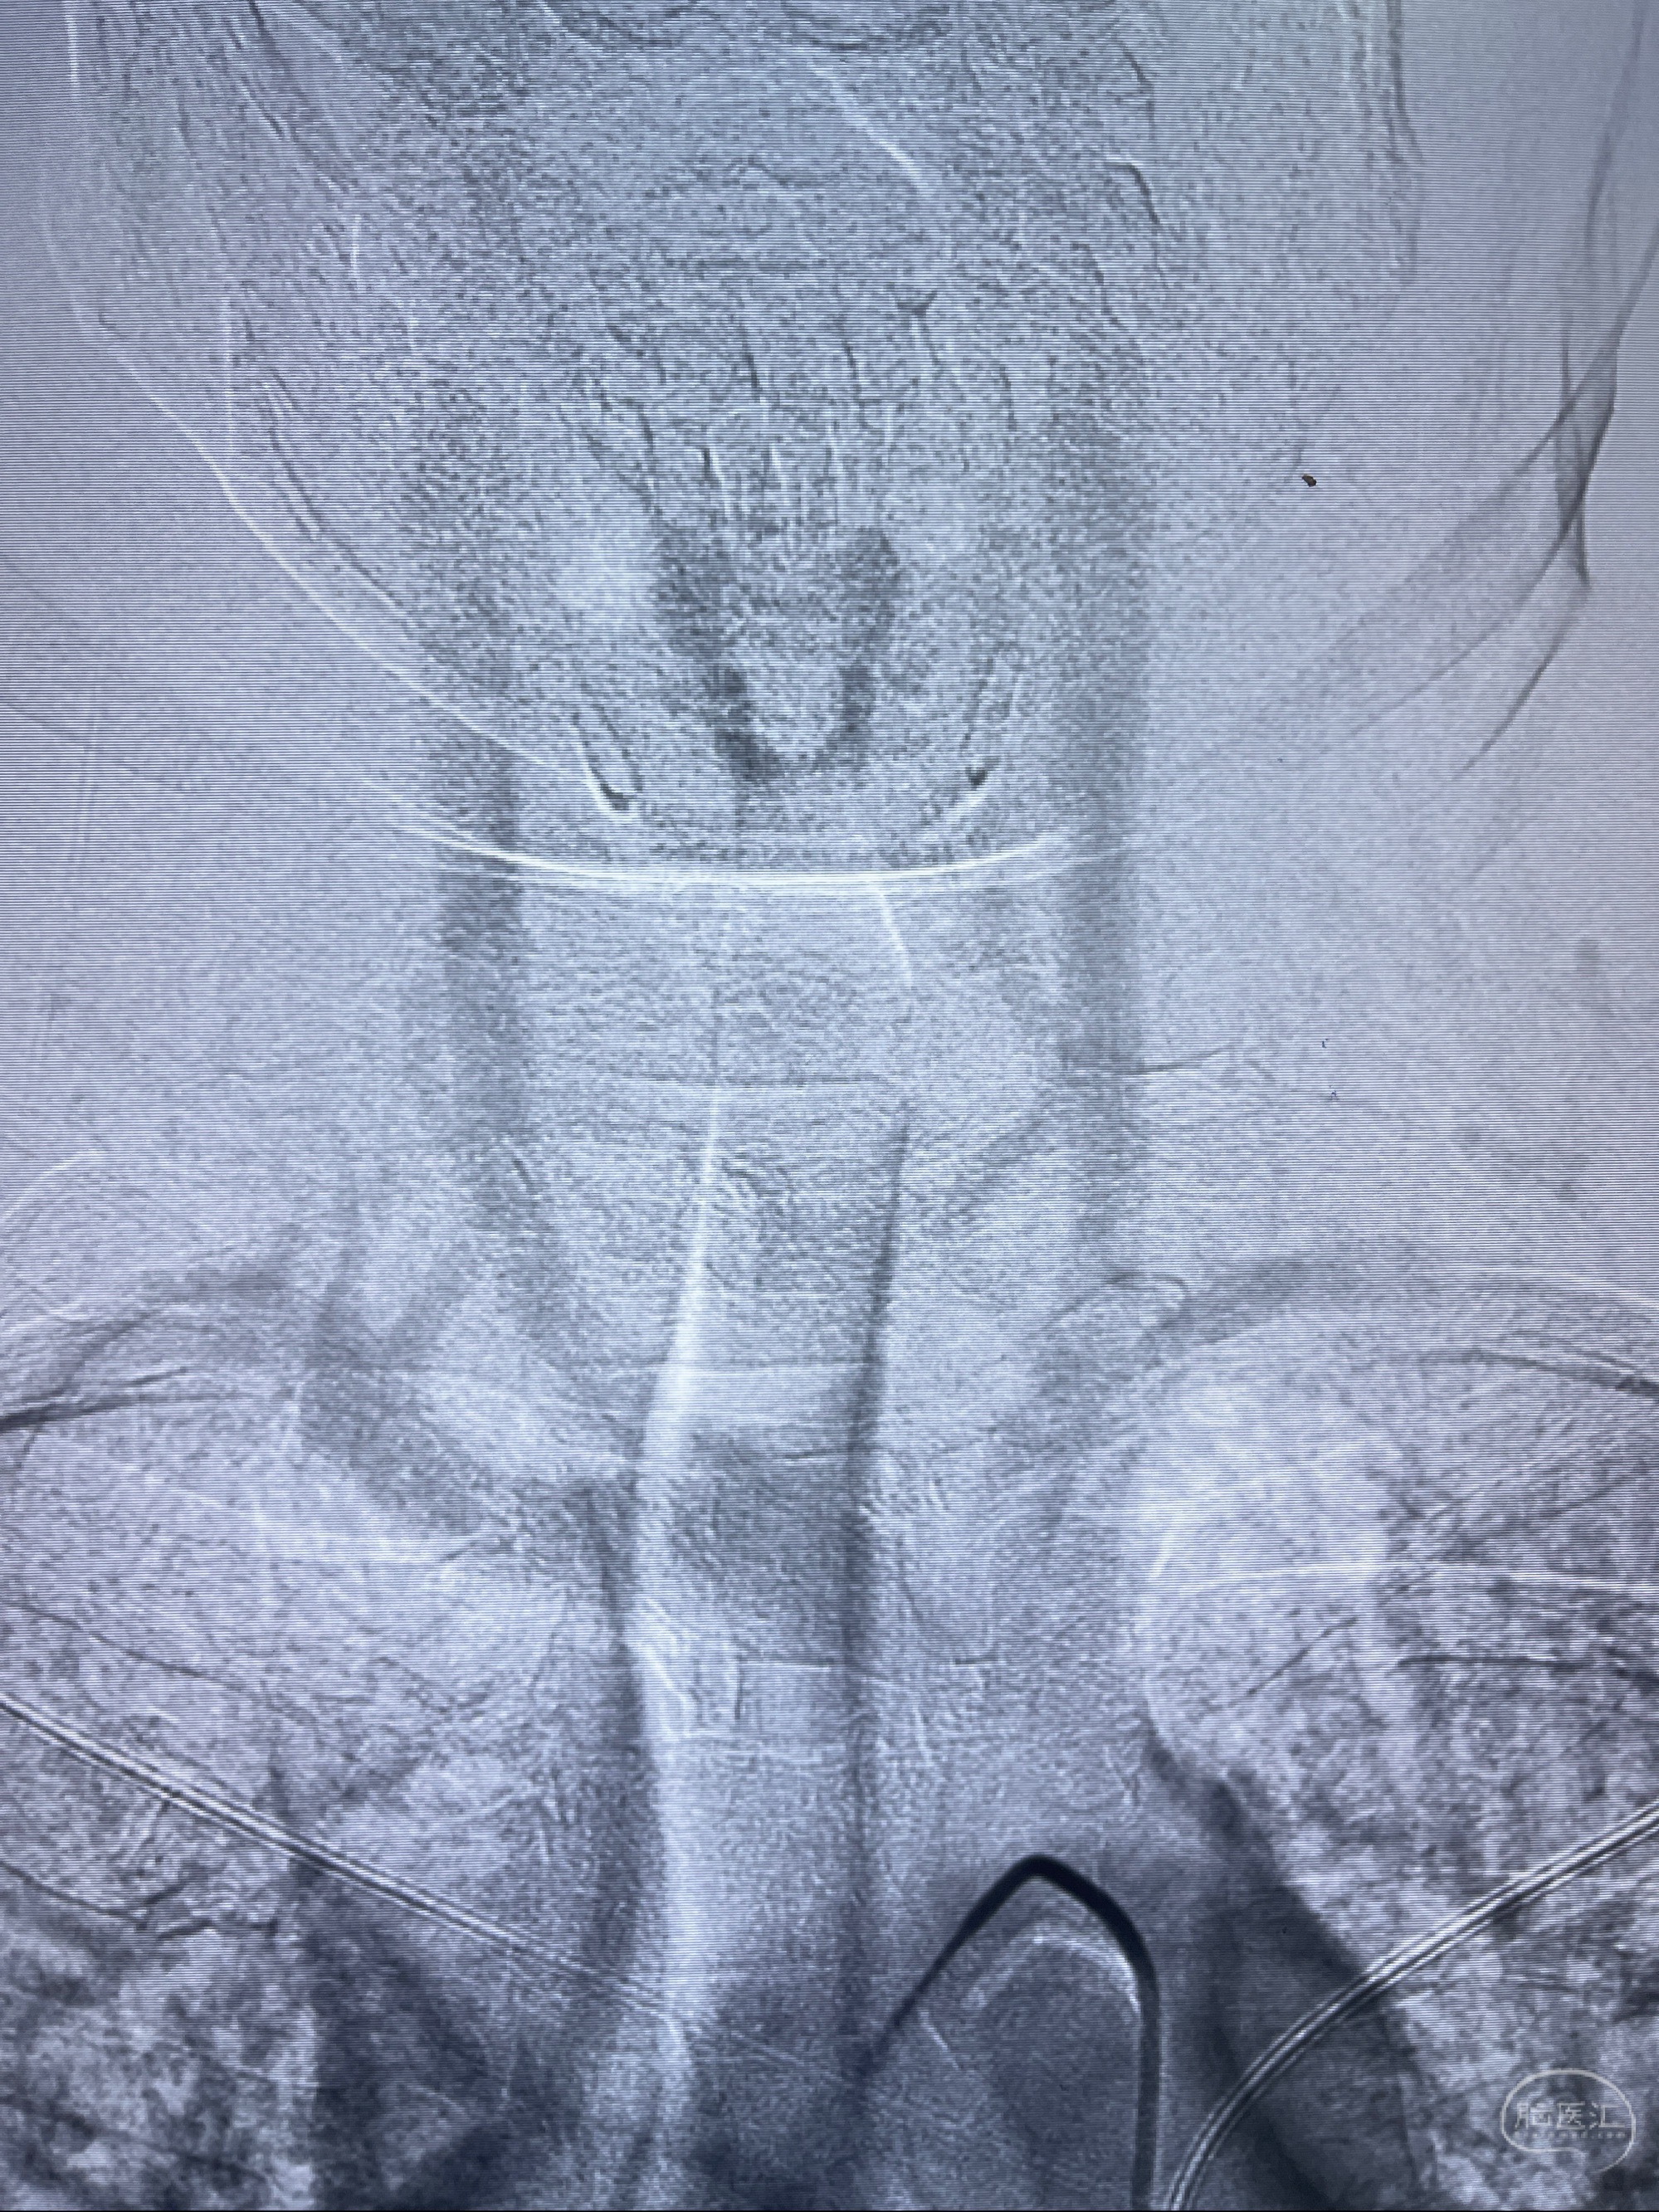

术后即刻CT